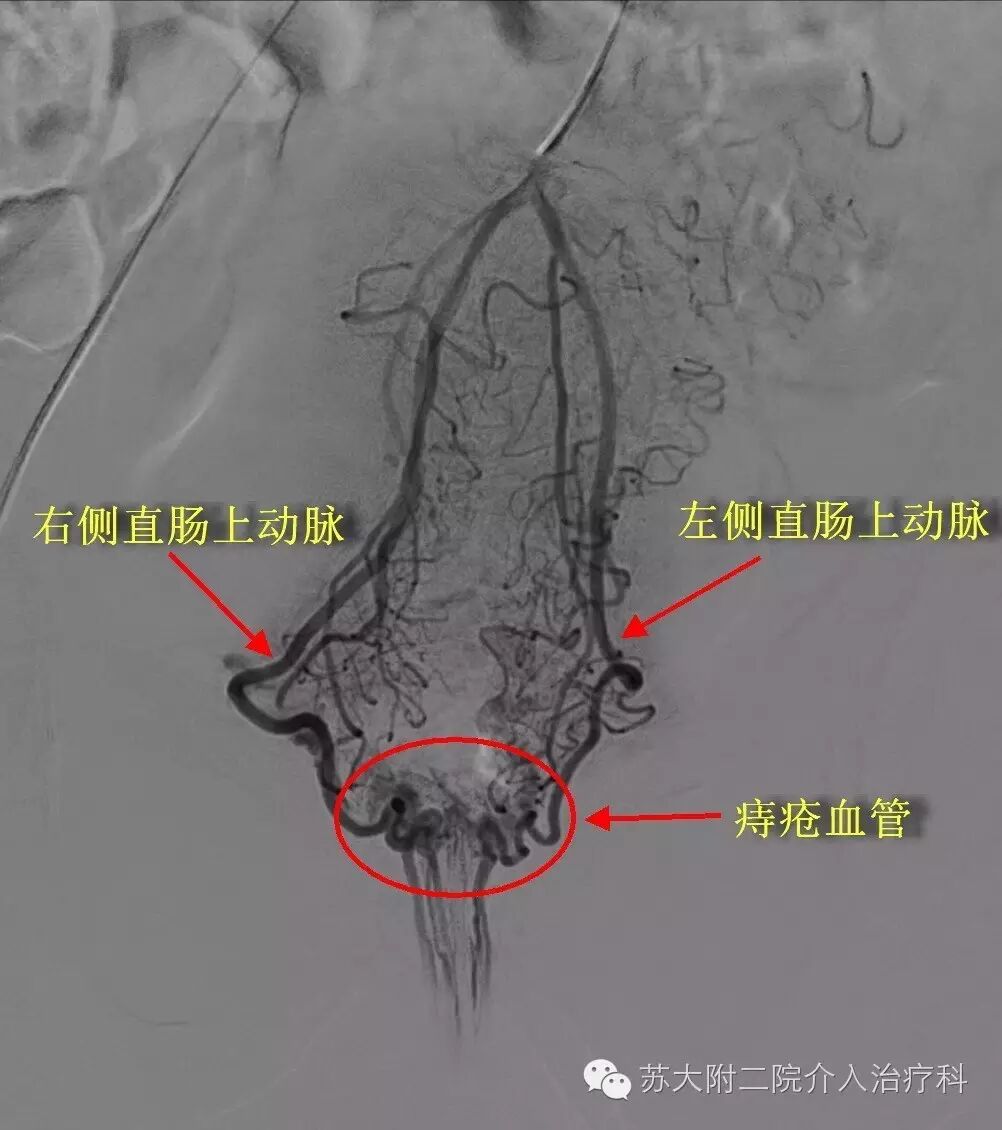

这是患者的栓塞前直肠周围动脉造影的图片,可见左右直肠动脉都明显变粗,在直肠肛管附近汇聚成粗大的引流静脉,就是给病人带来痛苦的痔疮。